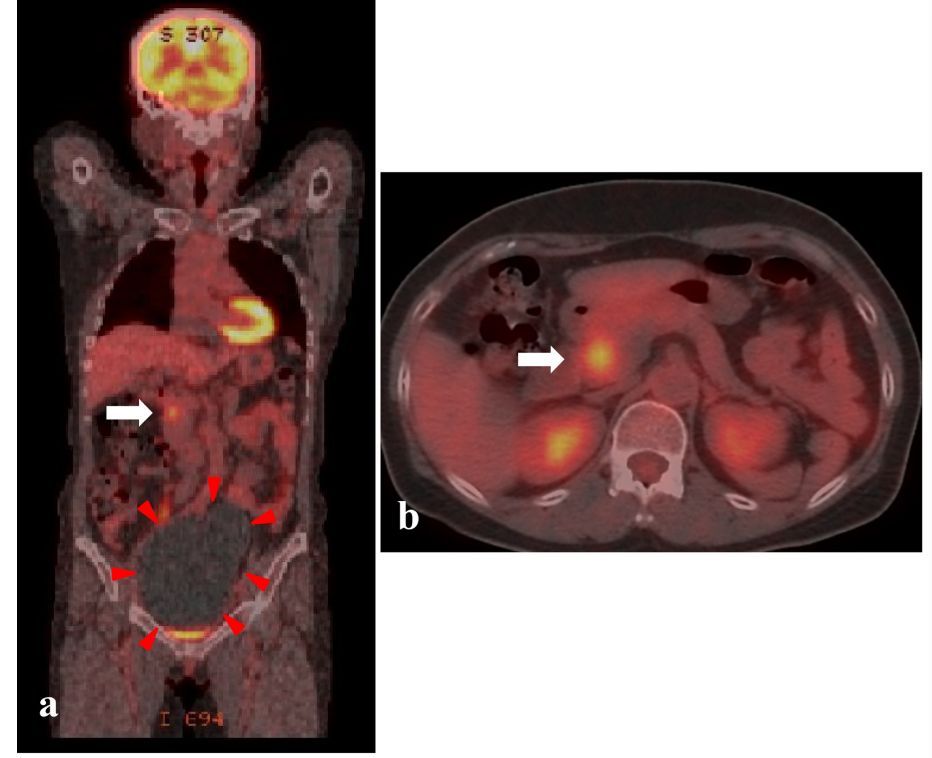

一名 59 岁女性,通过 CT 偶然发现胰头有一个 2 厘米大小的实性肿块。磁共振成像显示 T1 加权图像显示肿块为低信号,T2 加权图像显示肿块为异质性高信号。MRCP 显示主胰管未见异常。胰头肿块通过 FDG-PET/CT 显示胰头肿块的摄取明显增加。根据影像学表现,初步考虑了一个潜在的恶性肿瘤。

行保胃胰十二指肠切除术(SSSPD)以明确诊断。切除的标本显示在胰头有一个包裹良好的边界肿块,约 2.0 厘米。组织病理学检查显示肿瘤内梭形细胞增生,呈交错和栅栏状。增殖细胞无异型性,有丝分裂较少。免疫组化结果显示,梭形细胞中 S-100 蛋白呈阳性

图 2.1 FDG-PET/CT 显示代谢无增高囊性卵巢肿瘤(红色箭头)(a),胰头高代谢(SUV max 为 5.6)实性肿块(白色箭头)(a,b)。

由于 CT 和 MRI 的广泛应用,胰腺神经鞘瘤的偶然检出率预计将会增加。在胰腺肿瘤的鉴别诊断中,考虑到这种肿瘤是很重要的。此外,我们应该意识到,FDG-PET/CT 在良性胰腺神经鞘瘤中显示异常摄取。